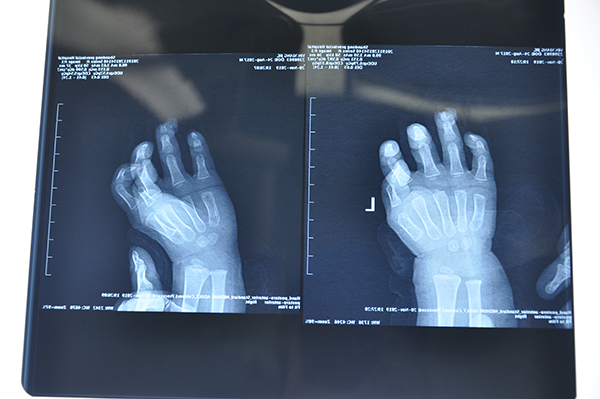

近日,山东省立医院东院区手足外科为一名2岁患儿进行婴幼儿指尖离断再植术,患儿环指指尖自指甲中远端1/3处离断再植成功。

11月20日晚9点,山东省立医院东院区手足外科急诊来了一个2岁的患儿,患儿右手环指指尖不慎被家中的健身器材挤伤,环指指尖自指甲中远端1/3处离断,离断指尖约绿豆粒大小,断面指骨外露,患儿急需要手术治疗。患儿及家属伤后前往多家医院就诊,均因手术难度大无法完成此手术,建议患者转诊。患者家属带着患儿抱着最后的希望来到山东省立医院就诊。

东院区手足外科二病区韩钦一医师接诊后,详细了解患儿病情后,考虑到患者为2岁小儿,血管本身就较成人血管细很多,而此患儿手指挤掉的部分又位于手指指尖处,需要吻合的血管直径要远小于0.2mm。小儿指尖再植手术对术者的显微外科技术要求高,技术难度大。向副主任医师王德华汇报病情后,决定收治该患儿并对其行急诊再植手术治疗。手术于当晚11点开始,到次日凌晨2点完成,经过3个小时的手术治疗,顺利完成清创、骨折固定、血管吻合,离断指尖通血红润,这个难度极大的接指手术成功完成。目前患者术后再植指尖成活良好。

Figure 3术前X片